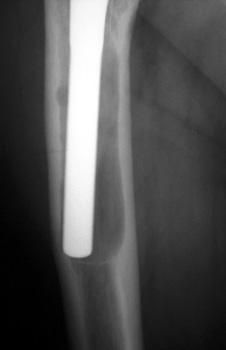

SUBSIDENCE - loose femoral prosthesis with interface widening,

osteolysis Gruen zone 6, cement fracture left femoral component

and osteolysis, with femoral component in valgus.